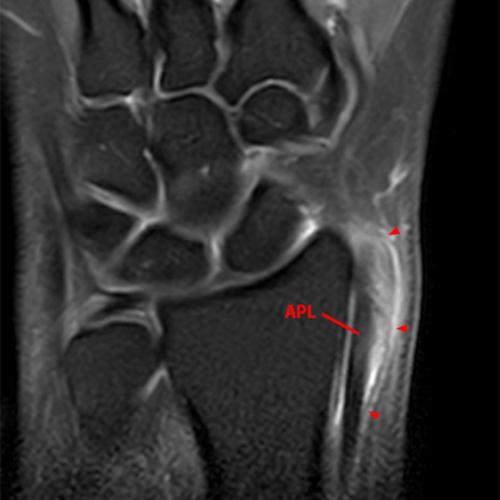

MRI: MRI is often unnecessary for diagnosing DQT, but it offers a more detailed view of soft tissues and can help visualize characteristic features of DQT. Fluid-sensitive imaging sequences show peritendinous edema surrounding the first extensor compartment tendons and extensor retinaculum. Tenosynovitis is identified as hyperintense fluid accumulation within the tendon sheaths on fluid-sensitive sequences. The thickened tendon sheath and tendon and surrounding edema are visible on MRI (Figure 8). Subjacent reactive marrow edema can also be seen (Figure 9). Although the accuracy of MRI has not been fully documented, it can identify multiple tendon slips and septations by utilizing the characteristic findings established by ultrasound.33 Visualization of a thin hypointense septation is easier with tenosynovitis and fluid distending the tendon sheaths, but it can be challenging. A double-groove appearance and a bony ridge of the radius floor of the first compartment can suggest the presence of a septum.

Figure 9: A 33-year-old female with radial-sided wrist pain for the evaluation of de Quervain’s tenosynovitis. Axial fat-suppressed proton density-weighted axial images at the proximal (9A) and mid-portion (9B) of the first extensor compartment demonstrate tenosynovitis with peritendinous fluid signal (arrows), overlying extensor retinacular and soft tissue edema, and marrow edema in the subjacent radius (arrowheads).